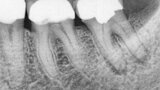

Fig. 17a: Case assisted with CBCT to determine anatomy pre-operatively. Note the multiple cross sections moving apically and the correlation to the 2-D view. Note also the conservative taper in relation to the root width. (Courtesy of Dr. Brett Gilbert)

Fig. 17b: Case assisted with CBCT to determine anatomy pre-operatively. Note the multiple cross sections moving apically and the correlation to the 2-D view. Note also the conservative taper in relation to the root width. (Courtesy of Dr. Brett Gilbert)